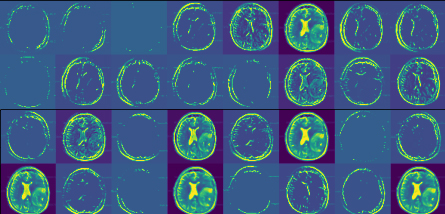

Training with the MRI dataset, which is made up of 150×\times150 gray-scale images, that is, each image is of shape (150,150,1) (Gray Scale = 1 channels). The sequential convolution feature extraction model is provided in Table 1 containing layer names, dimension, and parameters. Further, note that the CNN used in the experiment is also having the same architecture apart from the SVM classifier, which is replaced using a fully connected neural network. An example of the features extracted using a particular convolution layer on a particular slice is given as an example in Fig. 7. The generated feature vector will be used for the feature selection phase for reducing unnecessary features. LASSO regularization is used to select the optimal set of features and remove the features that may hamper the model performance. Convolutional feature extractor provides 2,49,536 features based on the total input data which has been significantly reduced to 5,240 features after LASSO feature selection is performed.

Refer to caption

Figure 7: Features extracted from a single slice in Block-1_Conv-1 layer.